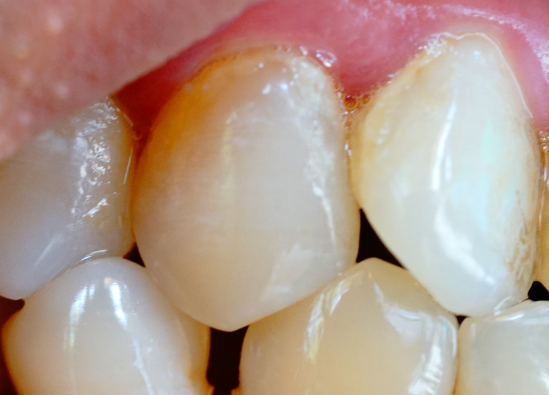

承德哪里可以治療牙縫過大

河北惟德口腔醫(yī)院小編提醒大家,牙齒牙縫變大,不僅影響我們正常的口腔牙齒健康以及平衡,而且還直接影響我們的正常生活飲食以及面部顏值。當(dāng)然這里面導(dǎo)致牙齒牙縫變大的原因有很多,不同原因的后果以及影響是不同的…